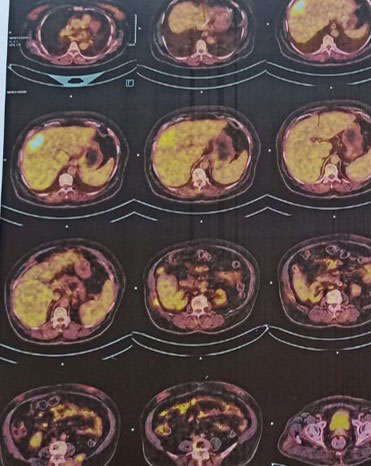

Radiology-

PET-CT revealed an FDG avid (SUV max 10.3), poorly circumscribed heterogeneous mass lesion measuring approximately 4.0 × 5.4 cm in the subcapsular region of segment VIII of liver with associated intralesional calcific foci. Background liver showed features of chronic liver disease with fatty change.